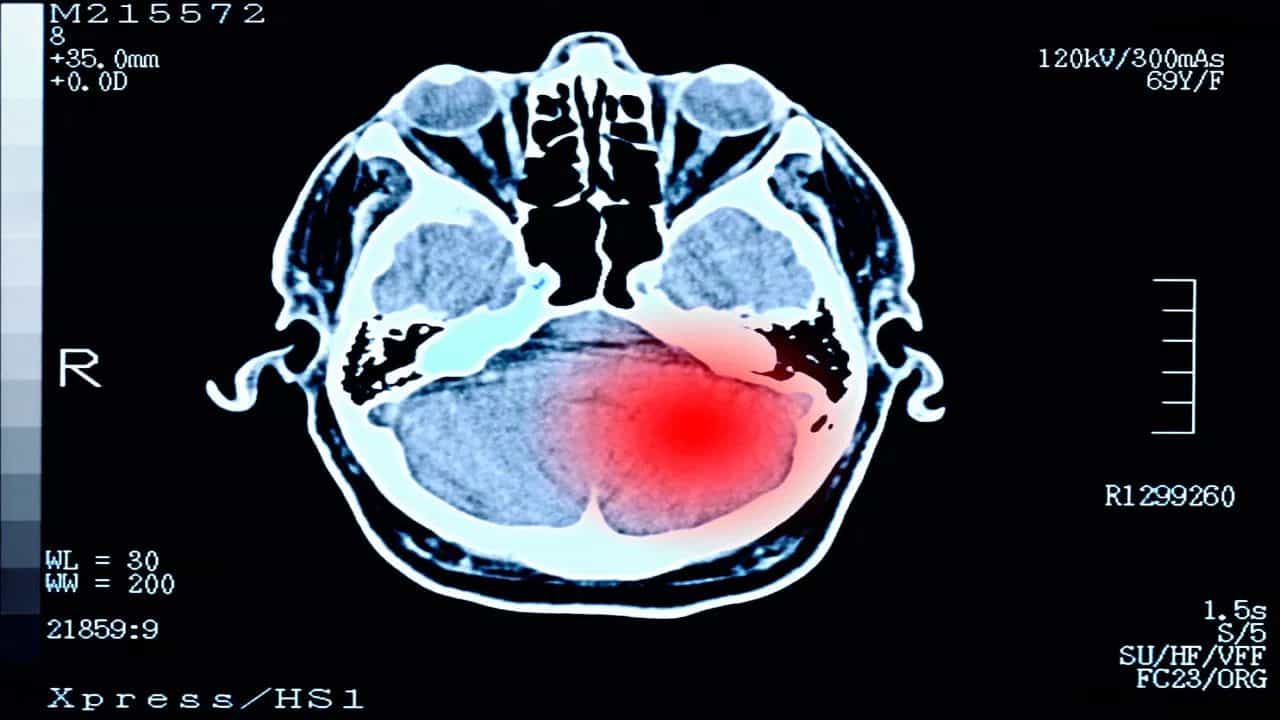

Brain Tumor

ਬ੍ਰੇਨ ਟਿਊਮਰ ਦੇ ਸਹੀ ਕਾਰਨਾਂ ਦਾ ਅਜੇ ਤੱਕ ਪਤਾ ਨਹੀਂ ਲੱਗ ਸਕਿਆ ਹੈ। ਹਾਲਾਂਕਿ, ਕੁਝ ਅਜਿਹੀਆਂ ਸਥਿਤੀਆਂ ਜ਼ਰੂਰ ਖੋਜੀਆਂ ਗਈਆਂ ਹਨ, ਜਿਨ੍ਹਾਂ ਕਾਰਨ ਬ੍ਰੇਨ ਟਿਊਮਰ ਦਾ ਖ਼ਤਰਾ ਸਭ ਤੋਂ ਵੱਧ ਹੁੰਦਾ ਹੈ। ਇਹਨਾਂ ਵਿੱਚੋਂ, ਜੈਨੇਟਿਕ ਕਾਰਨ ਮੁੱਖ ਹਨ। ਇਸ ਤੋਂ ਇਲਾਵਾ, ਕੁਝ ਰੇਡੀਏਸ਼ਨ ਦੇ ਸੰਪਰਕ ਵਿੱਚ ਆਉਣਾ ਅਤੇ ਨਿਊਰੋਫਾਈਬਰੋਮੇਟੋਸਿਸ ਇਸ ਦੇ ਮੁੱਖ ਕਾਰਨ ਮੰਨੇ ਜਾਂਦੇ ਹਨ। ਦਿਮਾਗ਼ ਦਾ ਟਿਊਮਰ ਕੁਝ ਮਾਮਲਿਆਂ ਵਿੱਚ ਲਾਇਲਾਜ ਹੁੰਦਾ ਹੈ। ਇਸ ਤੋਂ ਇਲਾਵਾ, ਜੇਕਰ ਦਿਮਾਗੀ ਟਿਊਮਰ ਕੈਂਸਰ ਵਾਲਾ ਹੈ ਤਾਂ ਸਰਜਰੀ ਤੋਂ ਬਾਅਦ ਵੀ ਜਾਨ ਦਾ ਖ਼ਤਰਾ ਰਹਿੰਦਾ ਹੈ। ਜਦੋਂ ਦਿਮਾਗ਼ ਵਿੱਚ ਟਿਊਮਰ ਹੁੰਦਾ ਹੈ ਤਾਂ ਸ਼ੁਰੂ ਵਿੱਚ ਕੁਝ ਲੱਛਣ ਸਾਹਮਣੇ ਆਉਂਦੇ ਹਨ।

ਹਾਲਾਂਕਿ, ਸਾਰੇ ਦਿਮਾਗ਼ ਦੇ ਟਿਊਮਰ ਕੈਂਸਰ ਵਾਲੇ ਨਹੀਂ ਹੁੰਦੇ; ਦਿਮਾਗ ਦੇ ਟਿਊਮਰ ਕਈ ਤਰ੍ਹਾਂ ਦੇ ਹੁੰਦੇ ਹਨ। ਇਨ੍ਹਾਂ ਵਿੱਚੋਂ, ਮੁੱਖ ਹਨ ਗਲੀਓਮਾ, ਕੋਰੋਇਡ ਪਲੇਕਸਸ ਟਿਊਮਰ, ਭਰੂਣ ਟਿਊਮਰ, ਜਰਮ ਸੈੱਲ ਟਿਊਮਰ, ਪਾਈਨਲ ਟਿਊਮਰ, ਮੈਨਿਨਜੀਓਮਾ, ਨਰਵ ਟਿਊਮਰ, ਪਿਟਿਊਟਰੀ ਟਿਊਮਰ। ਬ੍ਰੇਨ ਟਿਊਮਰ ਲਈ ਜੈਨੇਟਿਕ ਕਾਰਨ ਵੀ ਜ਼ਿੰਮੇਵਾਰ ਹਨ।